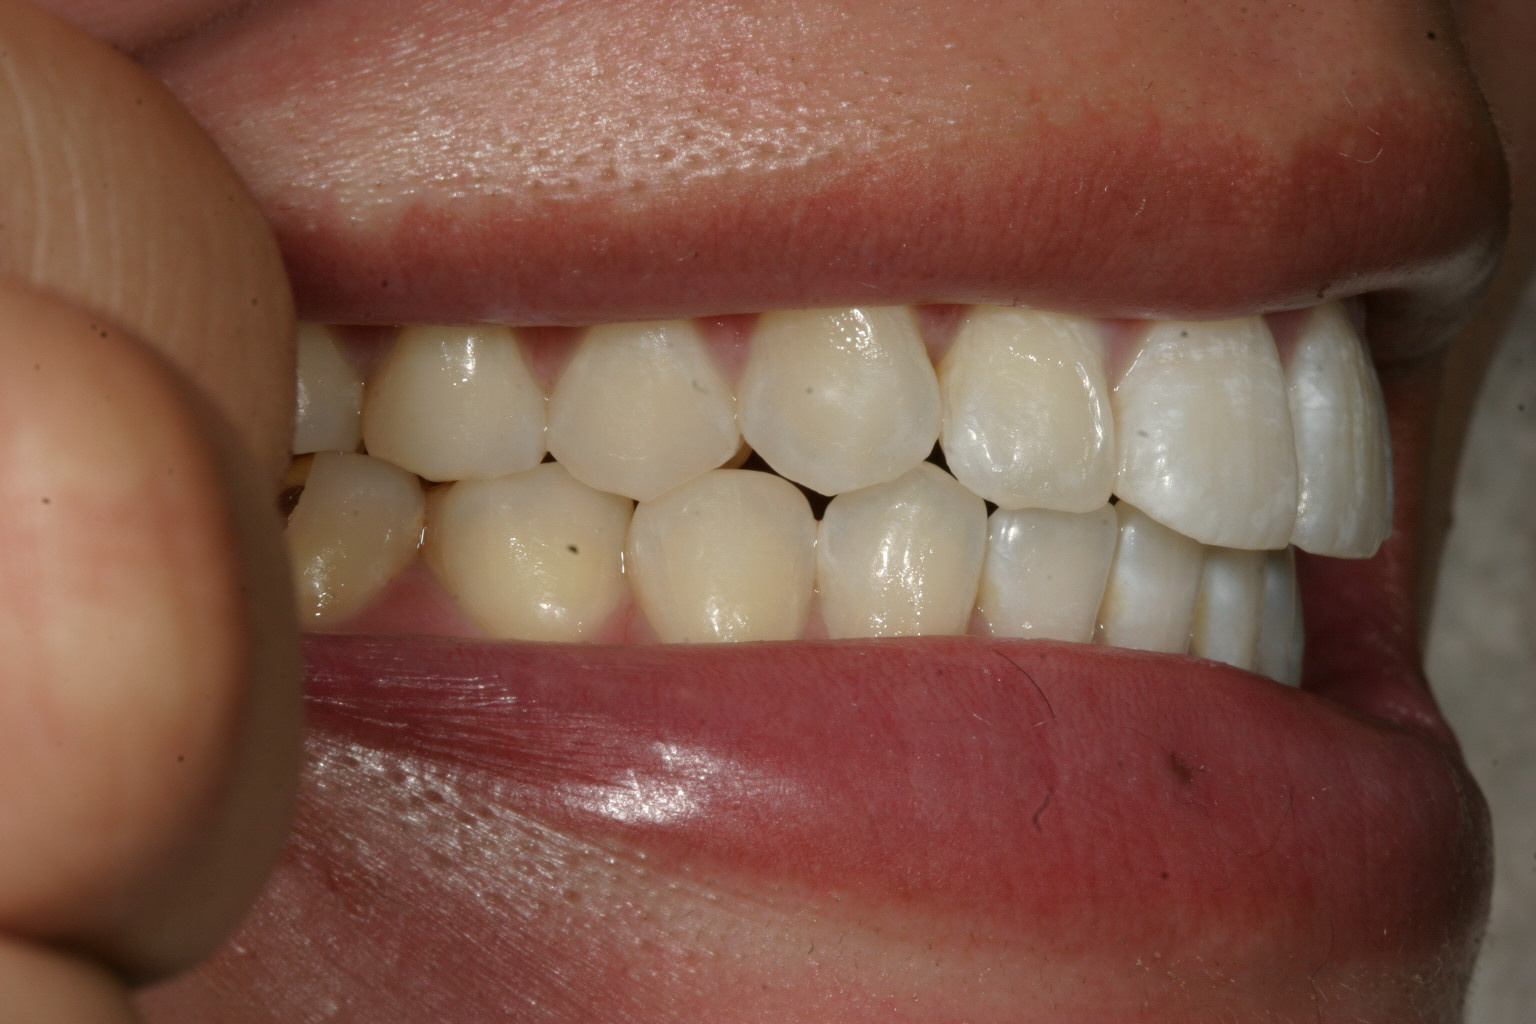

犬歯が飛び出して奥歯が上手く噛めていません。

綺麗に並びましたね〜

下顎も改善しました。

噛み合わせもバッチリです。